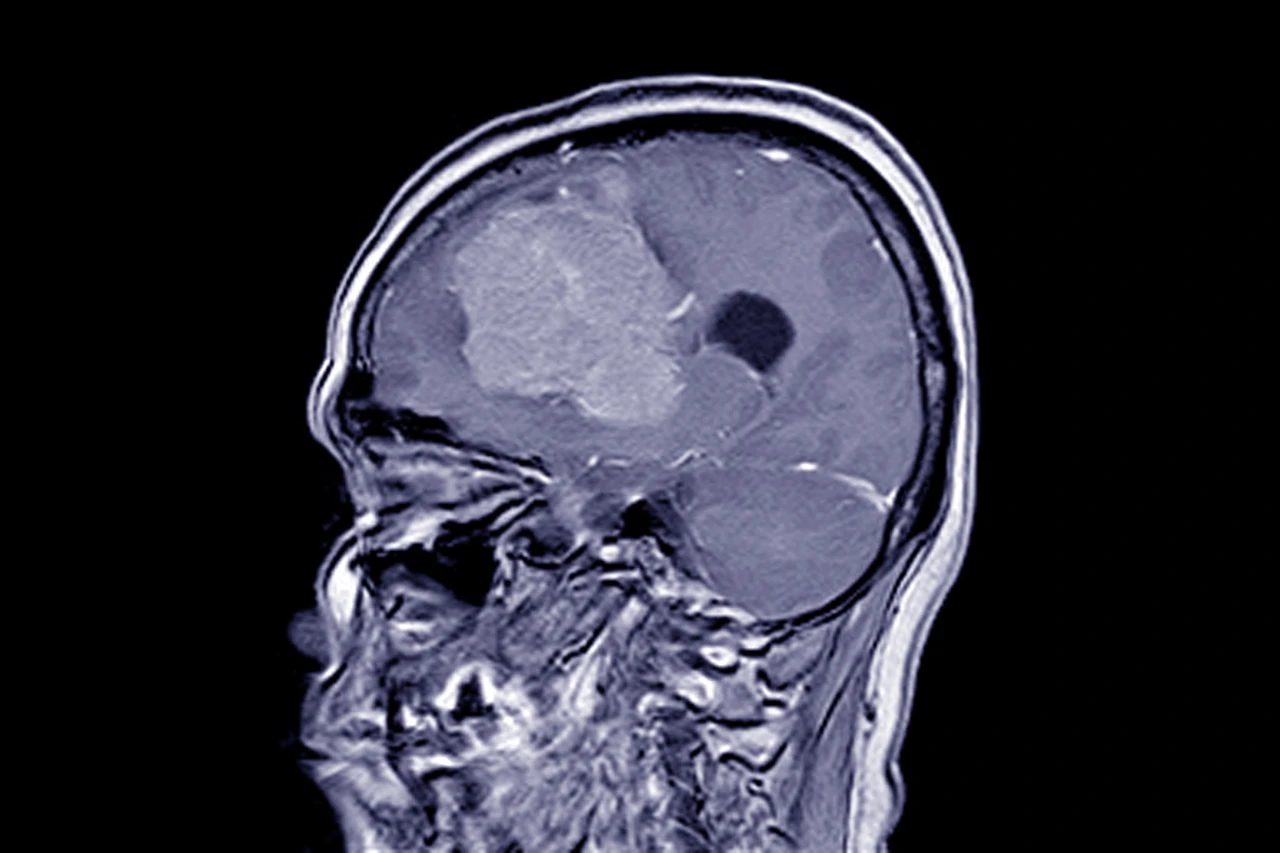

Менінгіома — це доброякісна пухлина, що утворюється з клітин оболонки мозку. Її поява часто залишається непоміченою роками, поки новоутворення не починає тиснути на структури мозку. Єдиним ефективним методом лікування у більшості випадків є хірургічне видалення. Але навіть після успішної операції людині потрібно знати, які можуть бути наслідки після видалення менінгіоми, щоб підготуватися до відновлення і уникнути ускладнень.

Менінгіома виникає через патологічне розростання клітин павутинної оболонки мозку. Найчастіше вона доброякісна, але навіть така пухлина може здавлювати нерви або судини. Залежно від розташування, операція може бути складною — нейрохірурги працюють поруч із життєво важливими ділянками мозку.

Основна мета втручання — максимально видалити пухлину, не пошкодивши навколишні тканини. Якщо пухлина розташована у важкодоступному місці або проросла у судини, хірург може залишити невелику частину, щоб уникнути серйозних наслідків. У такому випадку пацієнт потребує подальшого спостереження та, за потреби, радіотерапії.

Хоча більшість менінгіом є доброякісними, у 10–20% випадків можливе повторне утворення пухлини. Рецидиви зазвичай трапляються, якщо пухлину не вдалося видалити повністю або якщо вона мала агресивний характер.

Для своєчасного виявлення повторного росту пацієнтам рекомендовано проходити МРТ один раз на рік протягом перших кількох років після операції. При появі нових симптомів — головного болю, змін поведінки, судом — обстеження проводять негайно.